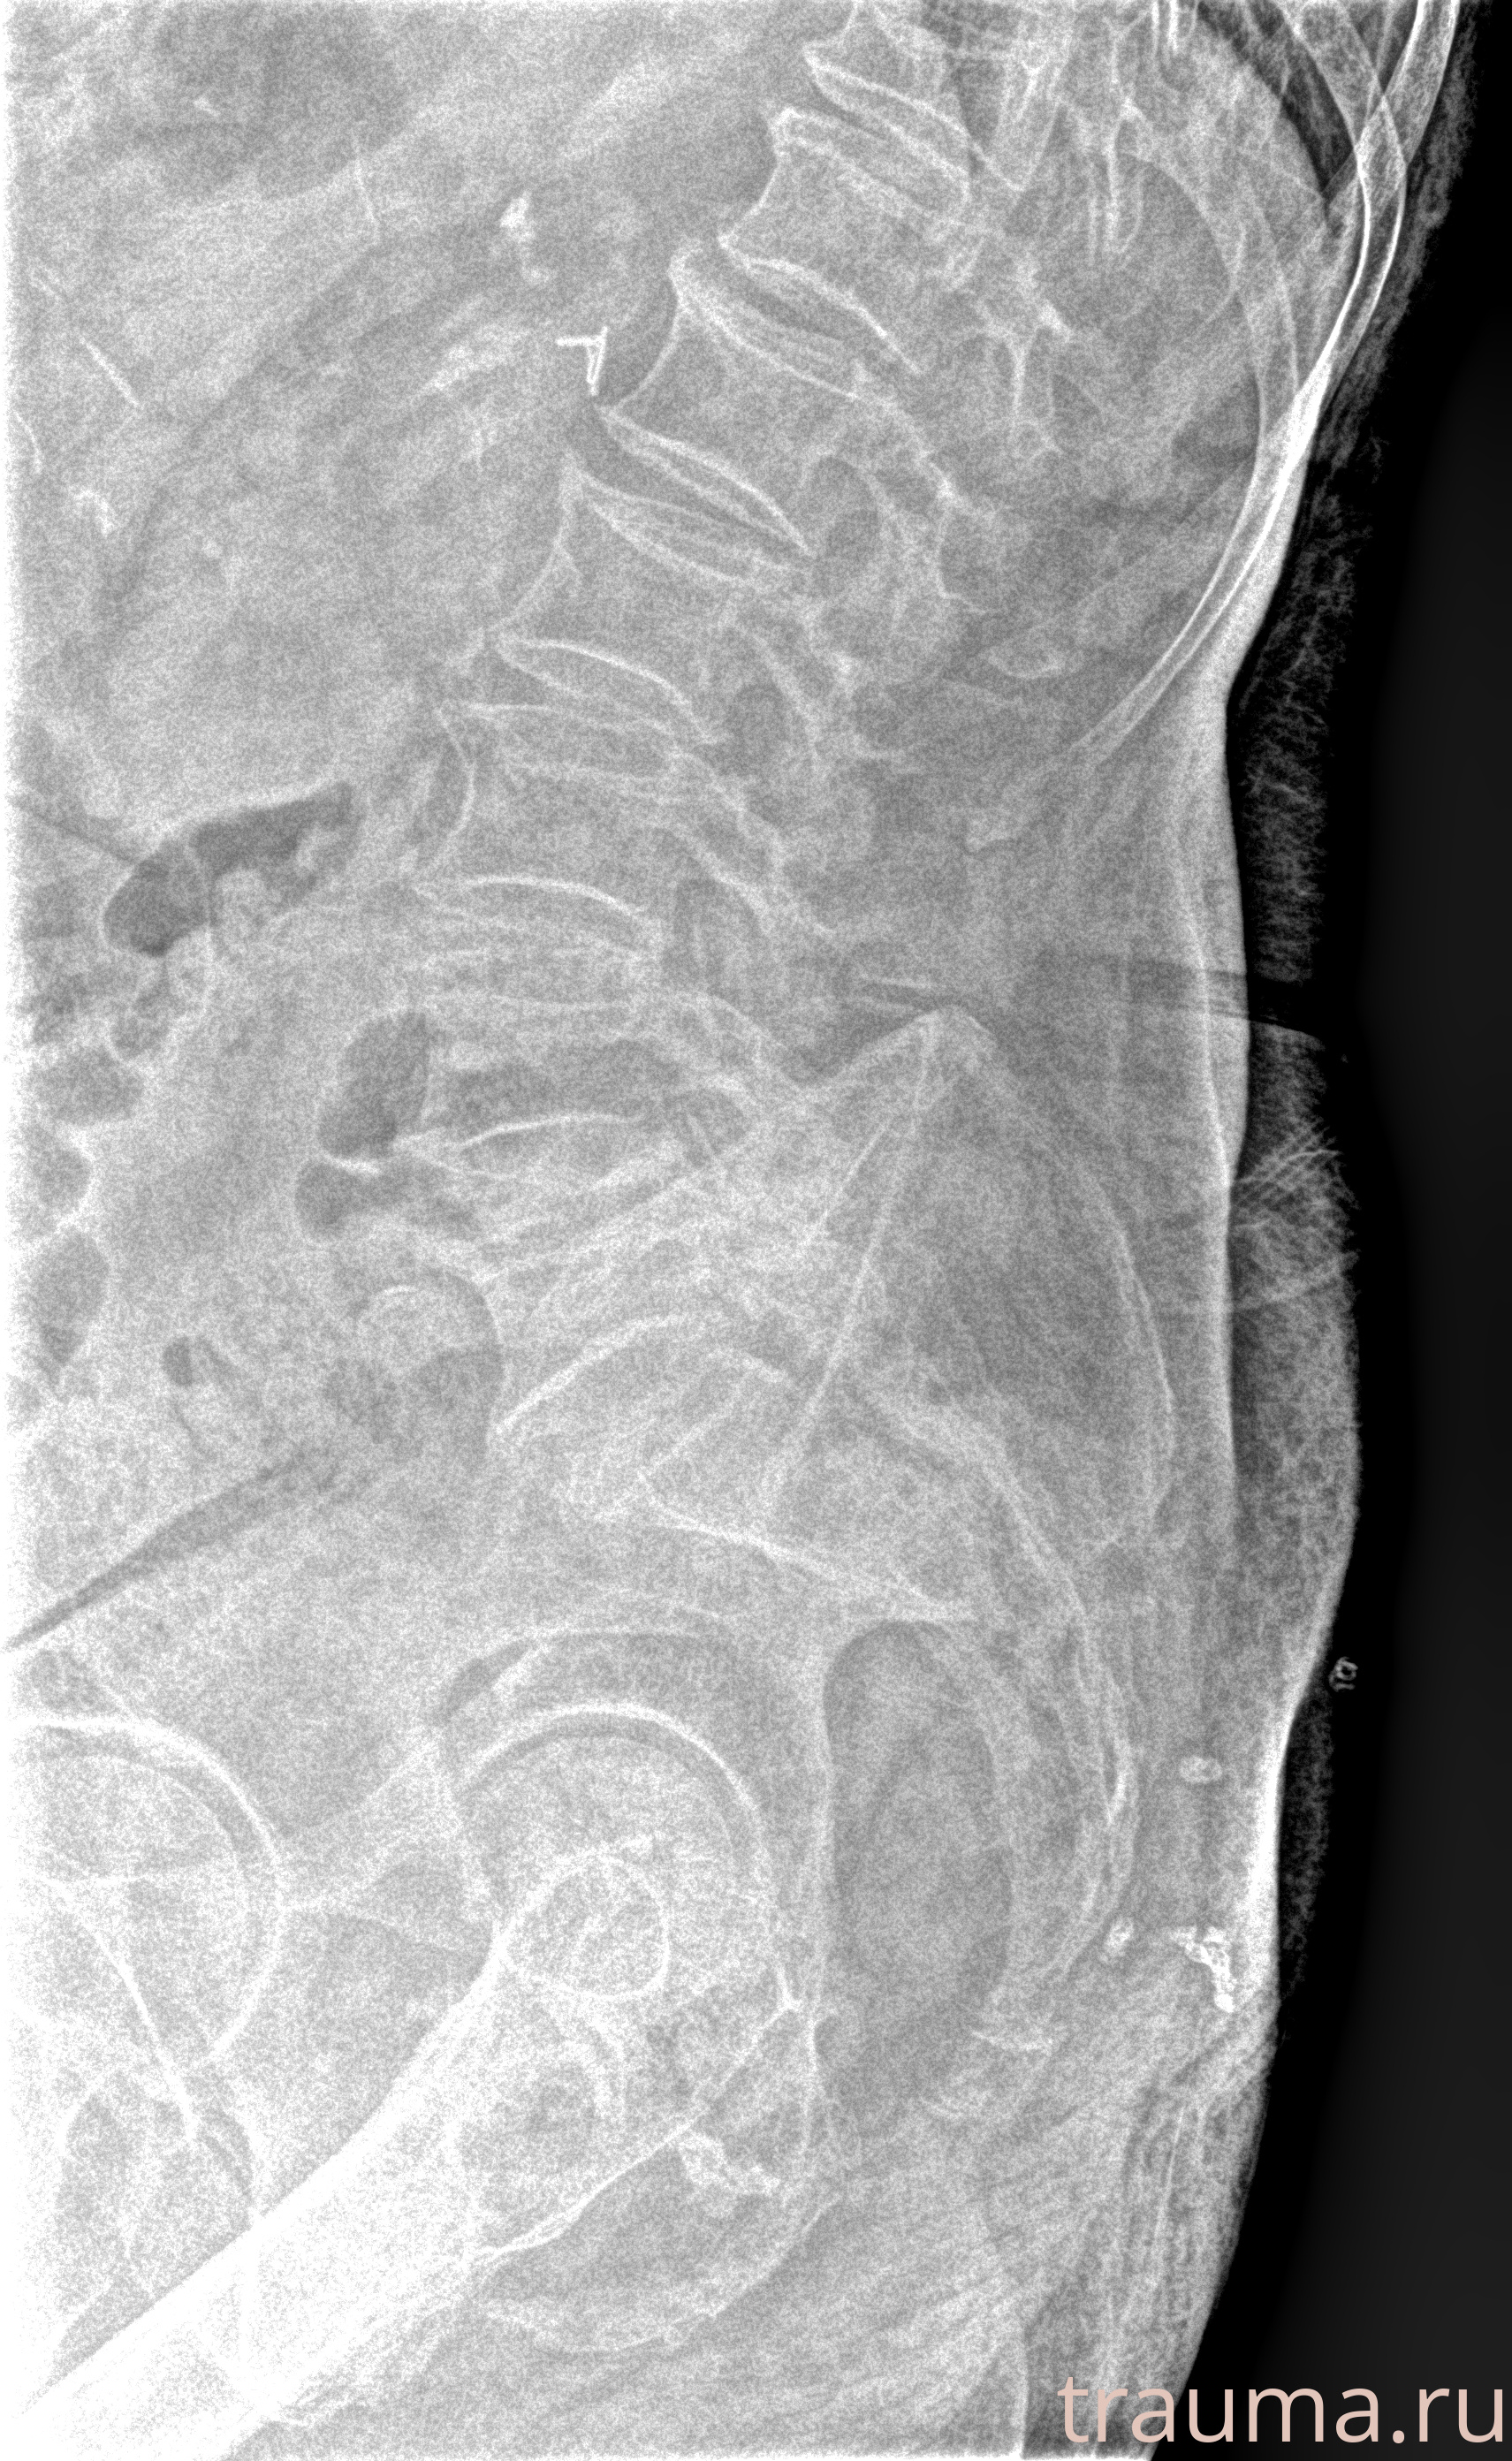

Рентген на дому: по вашему адресу приезжает врач-рентгенолог, травматолог-ортопед с мобильным рентгеновским аппаратом, проводит диагностику травмы или заболевания, делает необходимые рентгенограммы, дает рекомендации по дальнейшему лечению. Получить качественные снимки в домашних условиях возможно благодаря уникальной методике, разработанной МосРентген Центром для института  Склифосовского